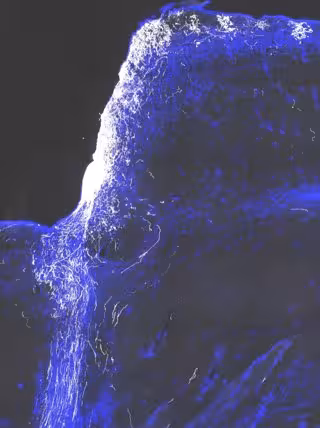

Como se informa en la edición digital de este jueves de la revista 'Cell', estos científicos restauraron la visión en ratones con lesión del nervio óptico mediante el uso de la terapia génica para conseguir que los nervios se regeneraran y --el paso crucial-- la adición de un fármaco de bloqueo de canal para ayudar a los nervios a llevar los impulsos desde el ojo hasta el cerebro. En el futuro, en su opinión, podría lograrse el mismo efecto sólo con medicamentos.

El reto fue que las fibras volvieron a crecer sin la vaina aislante conocida como mielina, que ayudan a propagar las señales nerviosas a través de largas distancias. "Encontramos que los axones regenerados no están mielinizados y tienen muy mala conducción; la velocidad de desplazamiento no es lo suficientemente alto como para sustentar la visión -dice He--. Necesitábamos una manera de superar este problema".

Aunque el estudio utilizó terapia génica con virus llamados AAV para administrar los factores de crecimiento que activan la regeneración (osteopontina, factor de crecimiento similar a la insulina 1 y factor neurotrófico ciliar), He y Fagiolini están probando si la inyección de un "cóctel" de proteínas del factor de crecimiento directamente en el ojo podría ser igualmente eficaz.